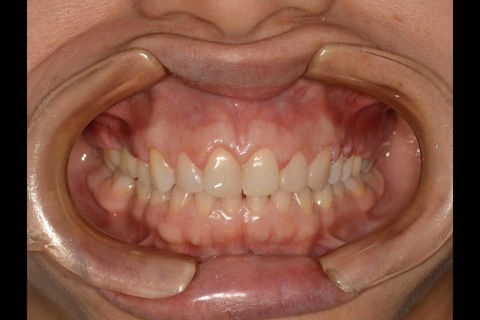

Fotos do caso